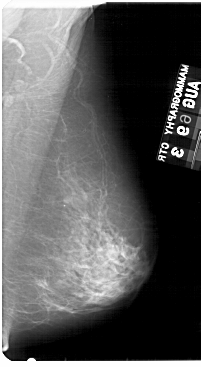

A_1954_1.LEFT_MLO

LEFT_MLO LINES 5491 PIXELS_PER_LINE 3361 BITS_PER_PIXEL 12 RESOLUTION 43.5 OVERLAY